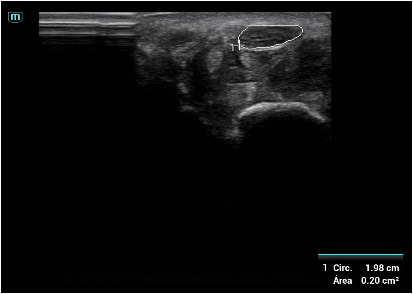

Descripción de los hallazgos ecográficos y las imágenes más relevantes para la resolución del caso

Signos de compresión del nervio mediano: área del nervio mediano 0,11 cc (> 9 patológico) con imagen en reloj de arena en la entrada del túnel del carpo.